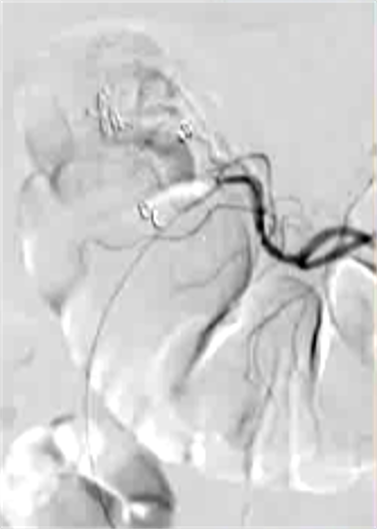

抗凝剂:肝素 溶栓药物:尿激酶、阿替普酶 ![]() 7 名患者 在动脉内内给予托拉唑啉、肝素、尿激酶进行血管造影操作 2 名患者出现出血性诱因情况 外科治疗 ![]() 回顾性分析(2002 年至 2008 年) 34 名患者(年龄 7 至 92 岁),36 例刺激性肠造影检查 全身性使用肝素 动脉内给药的血管扩张剂 11 名患者(占 31%)出现出血情况的检测结果。 10 栓塞治疗 病例1 消化道大出血 血压 70/40mmGg

病例三 77岁女性复发性胃肠道出血,需要多次输血并入住ICU。(d)栓塞后无外渗。箭头指向栓塞部位。

激发试验药物剂量和结果![]() 、、 ![]() 本文是一篇发表在《Journal of Gastrointestinal Surgery》上的研究通讯文章,题目为“Provocative Mesenteric Angiography: Outcomes and Standardized Protocol for Management of Recurrent Lower Gastrointestinal Hemorrhage”。该研究旨在评估激发肠系膜血管造影(PMA)在复发性下消化道出血中的有效性和并发症,并探讨是否可以在多学科环境中建立一种技术操作规程。 研究方法研究团队回顾了其机构在过去12年(2008年至2020年)期间进行的下消化道出血肠系膜血管造影的数据,基于CPT代码75726筛选出符合条件的病例。进一步分析了其中的PMA病例,排除了医源性、手术性或创伤性原因引起的下消化道出血。挑衅性造影的诱导方案包括使用硝酸甘油扩张血管、肝素抗凝以及组织纤溶酶原激活剂(tPA)溶解血栓。 研究结果在12年的研究期间,共进行了36例PMA。其中16例(44%)为阳性结果,20例(56%)为阴性结果。阳性组和阴性组之间在患者人口统计学特征、既往下消化道出血史、先前住院次数、Charlson合并症指数评分或术前血红蛋白水平方面没有显著差异。所有阳性病例均接受了栓塞治疗,且无出血并发症,无再出血事件,也未出现缺血性肠病后遗症。尽管有两名患者(12.5%)在30天内因复发性出血再次入院,但这一比例显著低于在阴性研究中再出血的60%。 结论本研究是迄今为止最大的文献,表明PMA在适当选择的患者中能够成功诱发和治疗下消化道出血。此外,该程序是安全的,即使使用较高剂量的tPA,也没有发生出血或缺血性肠病并发症。研究机构采用了一种修改后的现有社会指南协议,将PMA纳入下消化道出血的管理流程。 其他信息文章还提到了一些相关的参考文献和被引用的文章,涉及早期与标准结肠镜检查、急性下消化道出血的门静脉造影预测因素和结果、隐匿性胃肠出血的挑衅性肠系膜血管造影更新等内容。这些文献提供了更多的背景信息和相关研究支持。 激发血管造影并发症 与“激发”试验直接相关的并发症